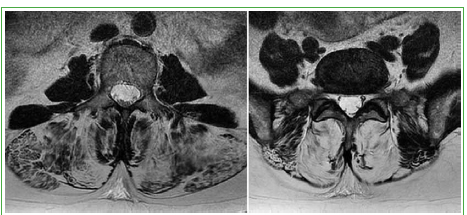

Figura 4.

Resonancia magnética, cortes axiales T2, de una mujer de 60 años con antecedentes de diabetes tipo 2 que manifiesta debilidad progresiva para mantener la postura erecta. En L3 y L5, se observa una masiva sustitución grasa de la musculatura erectora sin disminución del volumen del compartimento muscular.